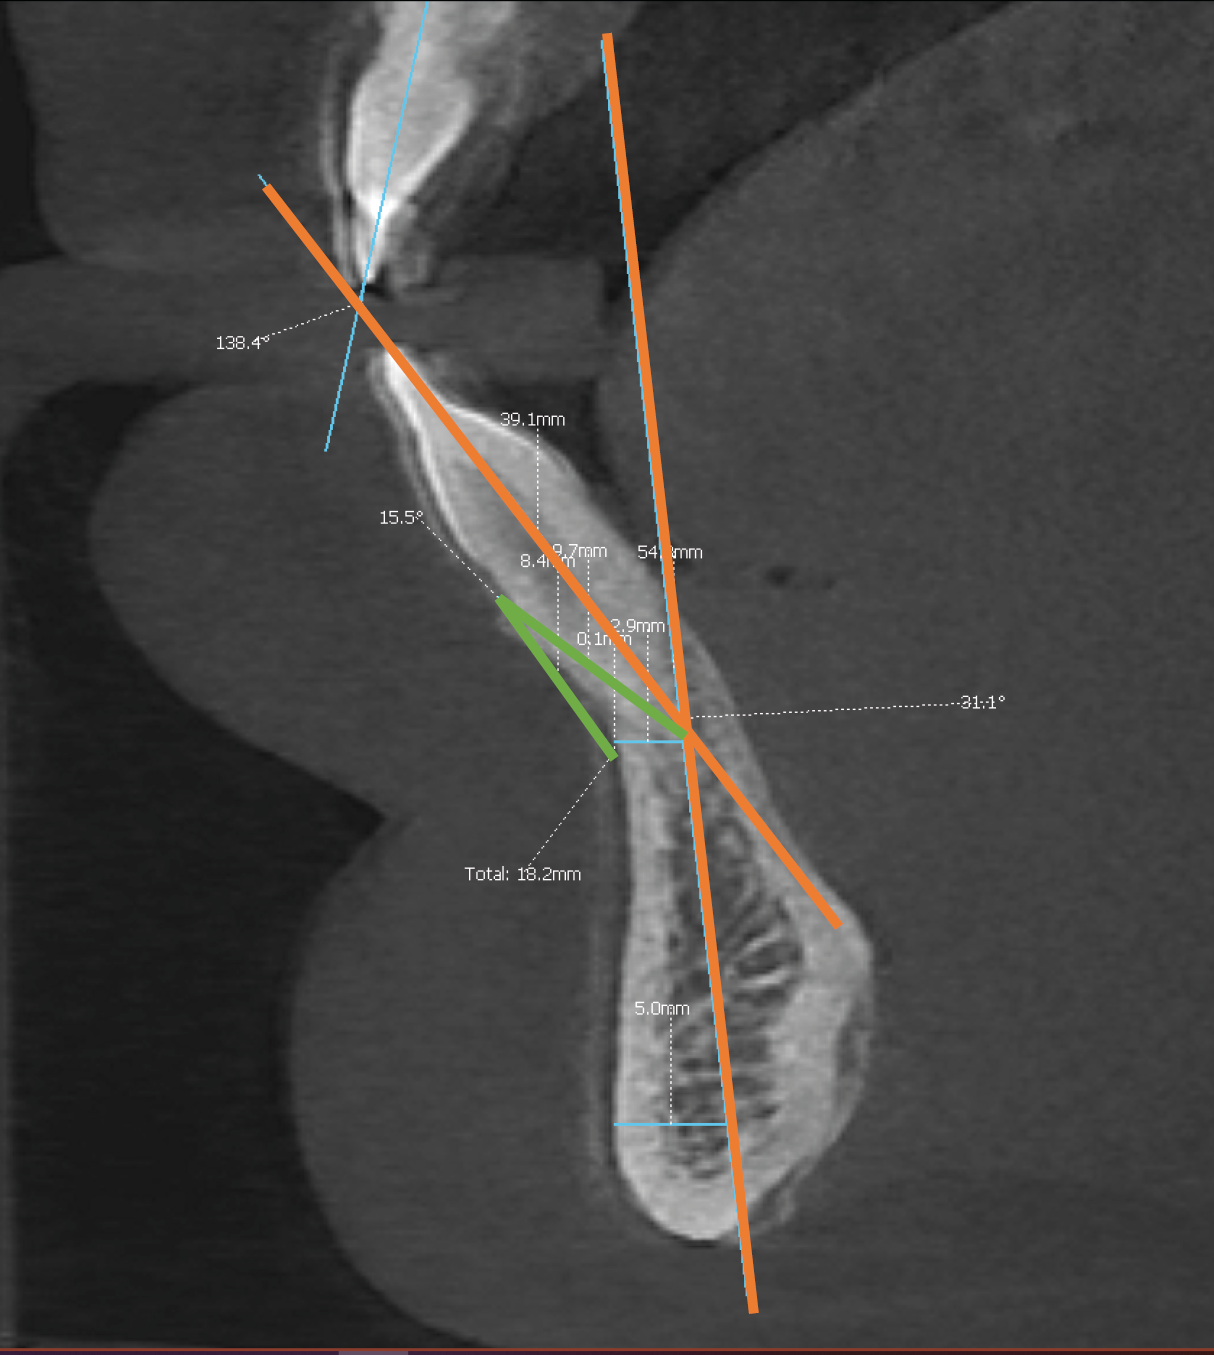

Angle between the long axis of the tooth and the long axis of mandible

The angle between the long axis of the tooth and the long axis of the mandible (1:Ml) was measured to assess tooth inclination; a larger angle indicated a more protruded tooth. This angle was measured on the sagittal plane of the CBCT using software tools, with a mean value ranging between 10° and 15°.13 The long axis of the tooth was defined as the line connecting the tip of the crown to the apical point of the most anterior mandibular central incisor (Iia). The long axis of the mandible was determined by identifying 2 points on the mandible and drawing a line between them: the 1st point was located at half the width in the tooth’s apex region, and the 2nd was set 5 mm above the inferior border of the mandible (Gnathion (Gn)). The half-width point was also measured (Figure 2).

API-CEJ2-B angle

The API-CEJ2-B angle was measured to assess the remaining labial bone in front of the teeth. Long lines were drawn connecting the following points: the deepest point on the anterior concavity of the mandibular symphysis (point B), the apical point of the most anterior mandibular central incisor (Iia), and the point located 2 mm apical to the cementoenamel junction (CEJ) of the incisor (Figure 2), which reflects the sulcus depth.22

The method for measuring the width of the mentalis muscle was proposed by Dominiak.22 Assessing this width helps estimate muscle tension and hyperactivity. In her method, a new landmark, point “D,” is defined on the soft tissue. To locate point D, a “GoGn” line is drawn between the Gnathion and Gonion points. Additionally, point “B” is identified as the deepest point on the mandibular concavity. Next, a line parallel to the GoGn line is drawn through point B, and its intersection with the soft tissue border marks point D. The width of the mentalis muscle on the sagittal plane is then defined as the distance between points B and D (B:D) (Figure 3).